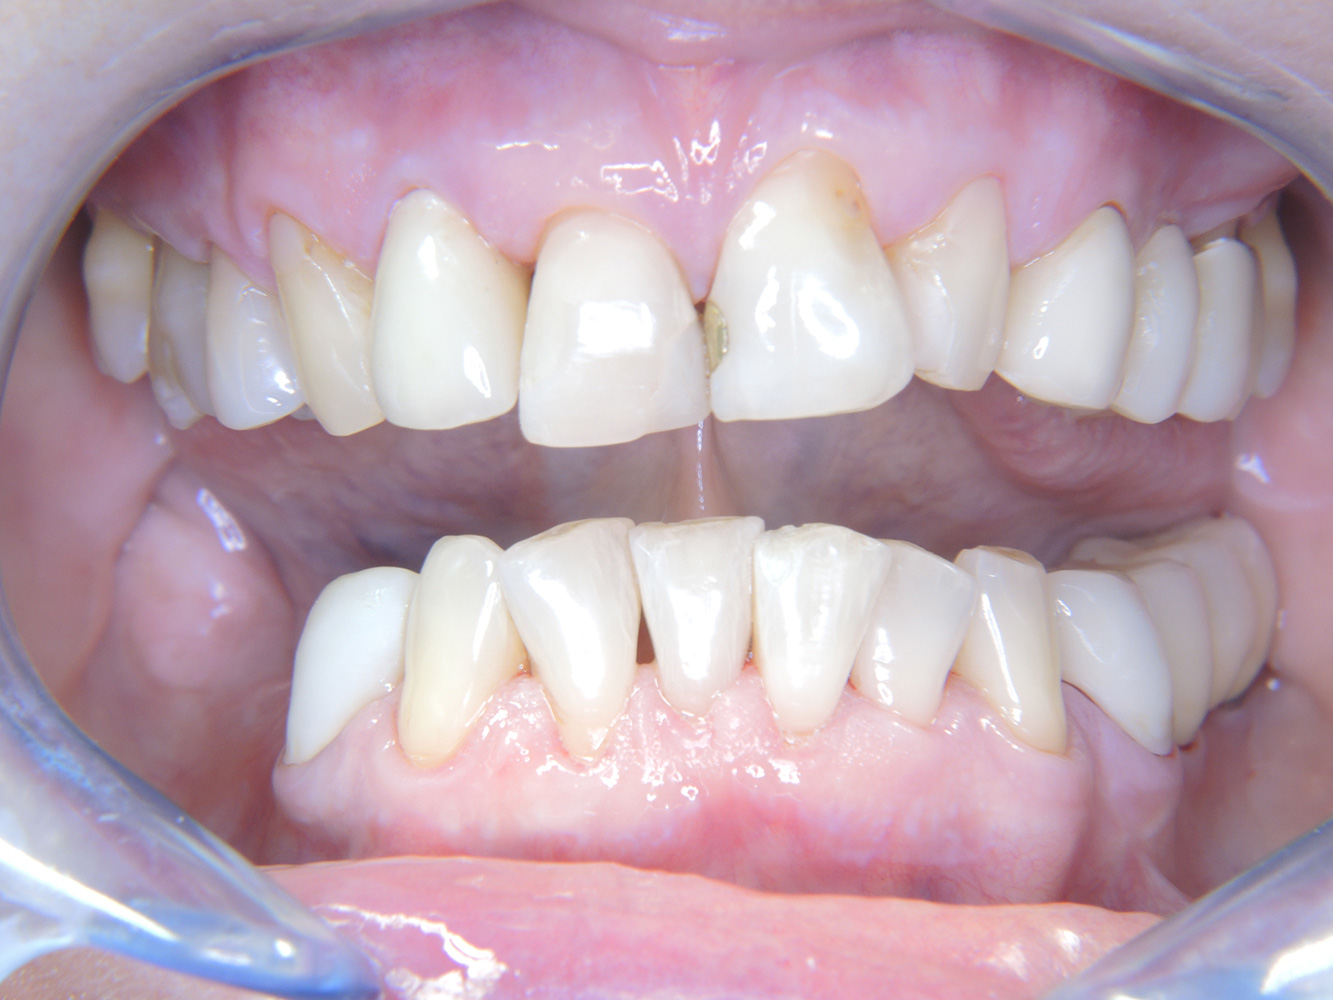

Die 68-jährige Patientin hat keine zahnmedizinisch relevanten allgemeingesundheitlichen Vorerkrankungen oder Medikation, auch aus dem Lebensstil ergibt sich kein besonderes Risiko. Die Patientin hat zwei Implantate (3. Quadrant, seit fünf Jahren) sowie eine parodontale Vorerkrankung (Parodontitis Stadium IV, Grad B) mit Zahnverlust. Derzeit zeigen sich stabile parodontale Verhältnisse, jedoch erhöht Parodontitis maßgeblich die biologischen Komplikationen bei Implantationen und es droht der Implantatverlust (21).